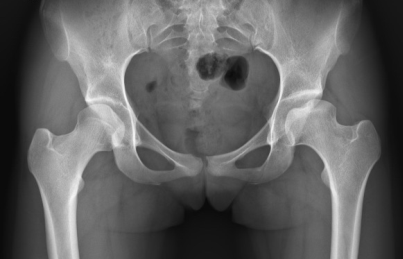

К ранним симптомам болезни коксартроз можно отнести: ноюще-колющие боли в области тазобедренного сустава, хромоту по утрам, прекращающуюся со временем, небольшую ограниченность в движении [4]. На данном этапе физикальное лечение и лечебная физическая культура (ЛФК) могут привести к восстановлению сустава (Рис. 2).

Рис. 2. Этап восстановления левого тазобедренного сустава